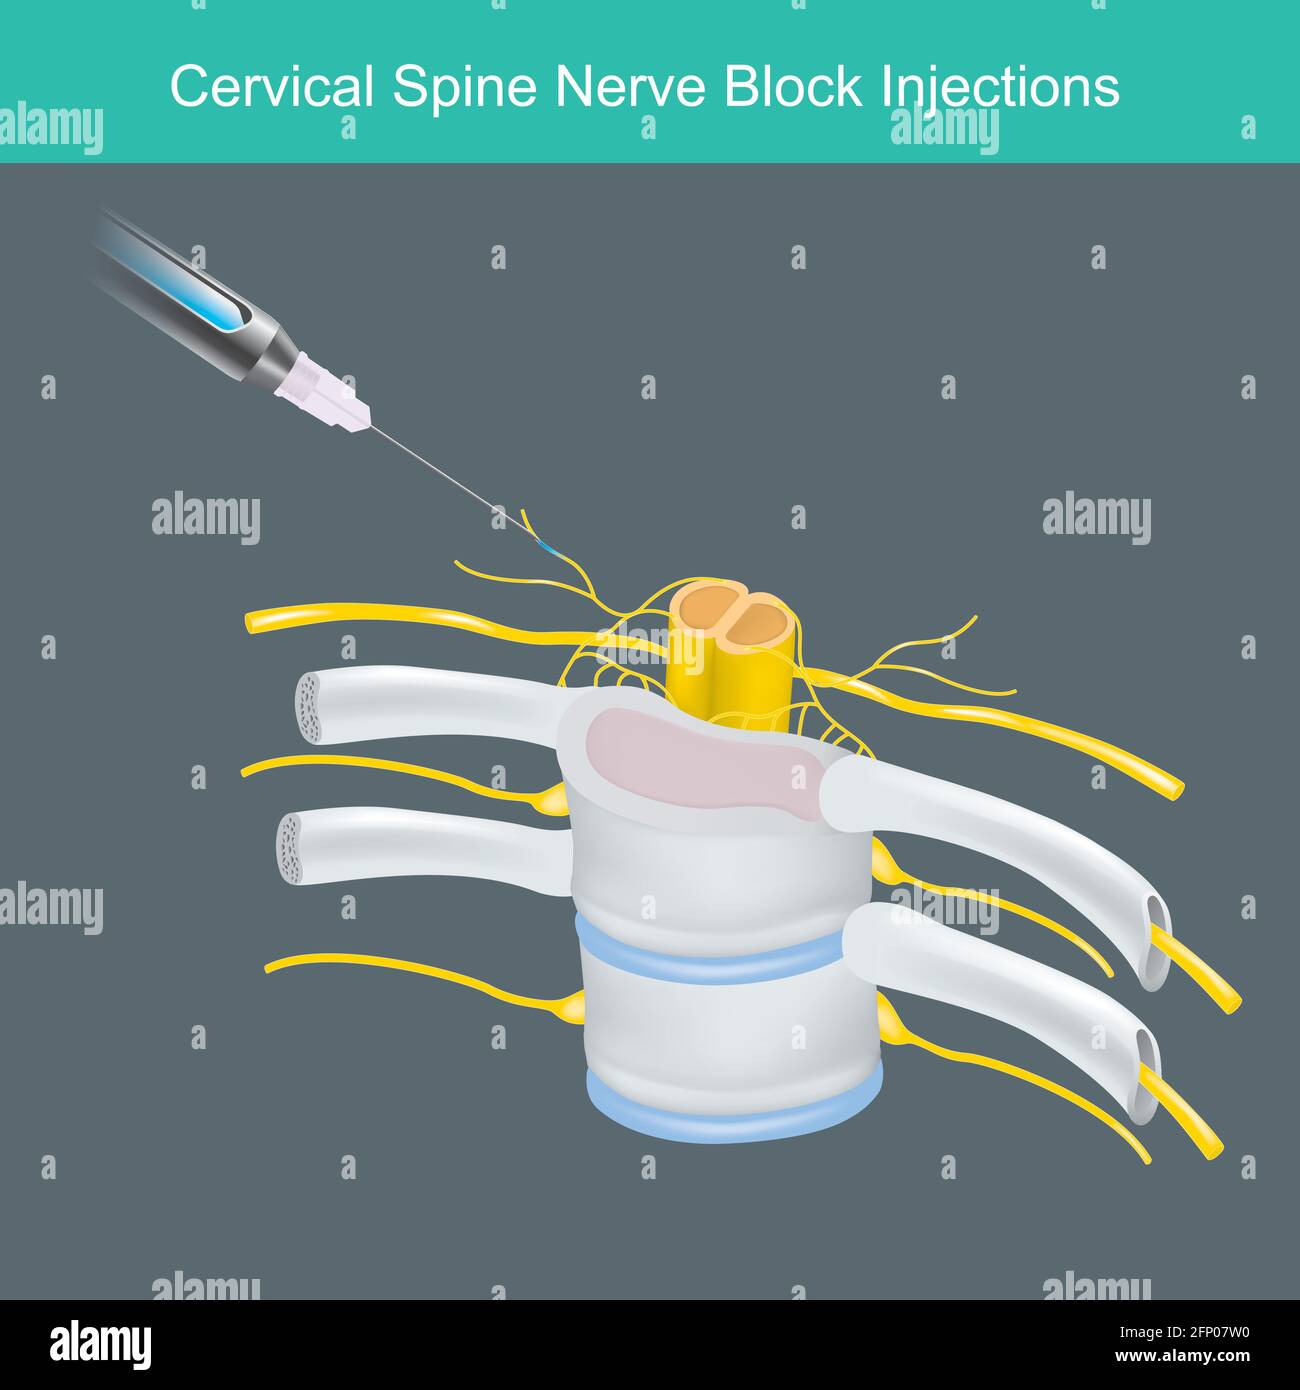

Iniezioni di blocco nervo della colonna cervicale. Illustrazione per l'apprendimento della soluzione anestetica iniettata il nervo della colonna cervicale del collo umano. Illustrazione Vettorialehttps://www.alamy.it/image-license-details/?v=1https://www.alamy.it/iniezioni-di-blocco-nervo-della-colonna-cervicale-illustrazione-per-l-apprendimento-della-soluzione-anestetica-iniettata-il-nervo-della-colonna-cervicale-del-collo-umano-image426577452.html

Iniezioni di blocco nervo della colonna cervicale. Illustrazione per l'apprendimento della soluzione anestetica iniettata il nervo della colonna cervicale del collo umano. Illustrazione Vettorialehttps://www.alamy.it/image-license-details/?v=1https://www.alamy.it/iniezioni-di-blocco-nervo-della-colonna-cervicale-illustrazione-per-l-apprendimento-della-soluzione-anestetica-iniettata-il-nervo-della-colonna-cervicale-del-collo-umano-image426577452.htmlRF2FP07W0–Iniezioni di blocco nervo della colonna cervicale. Illustrazione per l'apprendimento della soluzione anestetica iniettata il nervo della colonna cervicale del collo umano.